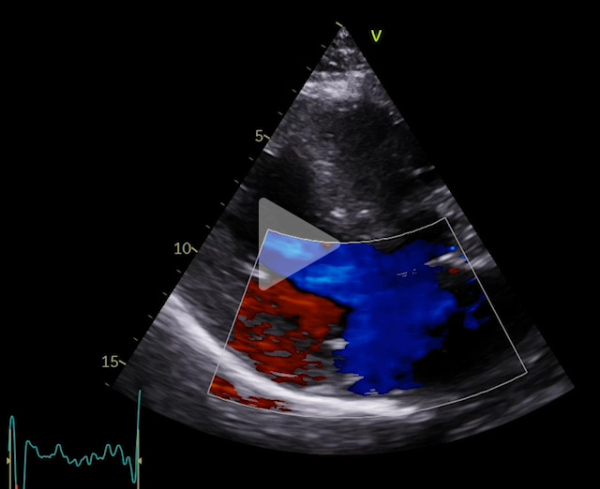

Voici son échocardiographie

Vidéo 2 : échocardiographie 2D en incidence parasternale grand axe avec doppler couleur